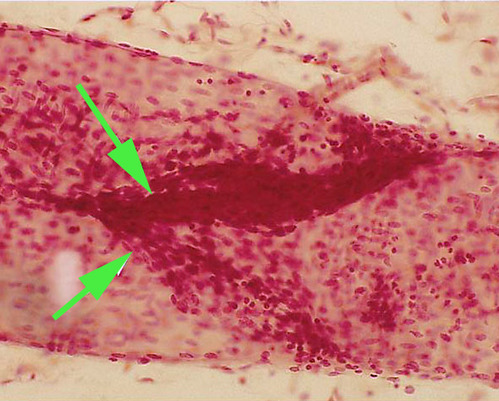

The structure labeled by the green arrows is a valve found in a lymphatic vessel.